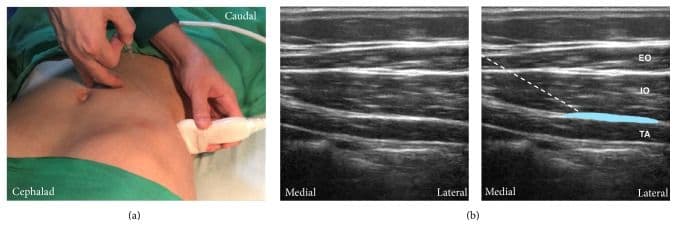

Середньоаксилярний ТАР-блок

Для виконання цієї блокади лінійний датчик розміщують в аксіальній площині по середній пахвовій лінії між краєм реберної дуги та гребенем клубової кістки. Візуалізують три шари м'язів стінки: зовнішній та внутрішній косі м'язи живота, а також поперечний м'яз живота. Ціллю є фасціальна площина між внутрішнім косим м'язом живота та поперечним м'язом живота. Голку вводять по передній пахвовій лінії, і кінчик голки просувають до досягнення фасціальної площини між внутрішнім косим м'язом живота та поперечним м'язом живота приблизно по середній пахвовій лінії [5,6,13,25].